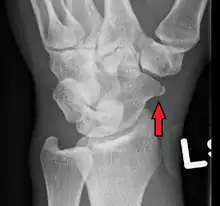

A subtle scaphoid fracture

Scaphoid fractures are often diagnosed using plain radiographs and multiple views are obtained as standard.[9] However, not all fractures are apparent initially.[7] In 1/4 of cases, the clinical examination suggests a fracture, but the X-ray does not show it, even though there is indeed a fracture.[10] Therefore, people with tenderness over the scaphoid (those who exhibit pain to pressure in the anatomic snuff box ) are often splinted in a thumb spica for 7–10 days at which point a second set of X-rays is taken.[7] If a minimally displaced fracture was present initially, healing will now be apparent. Even then a fracture may not be apparent. A CT Scan can then be used to evaluate the scaphoid with greater resolution. The use of MRI, if available, is preferred over CT and can give one an immediate diagnosis.[11] Bone scintigraphy is also an effective method for diagnosis fracture which do not appear on Xray.[12]